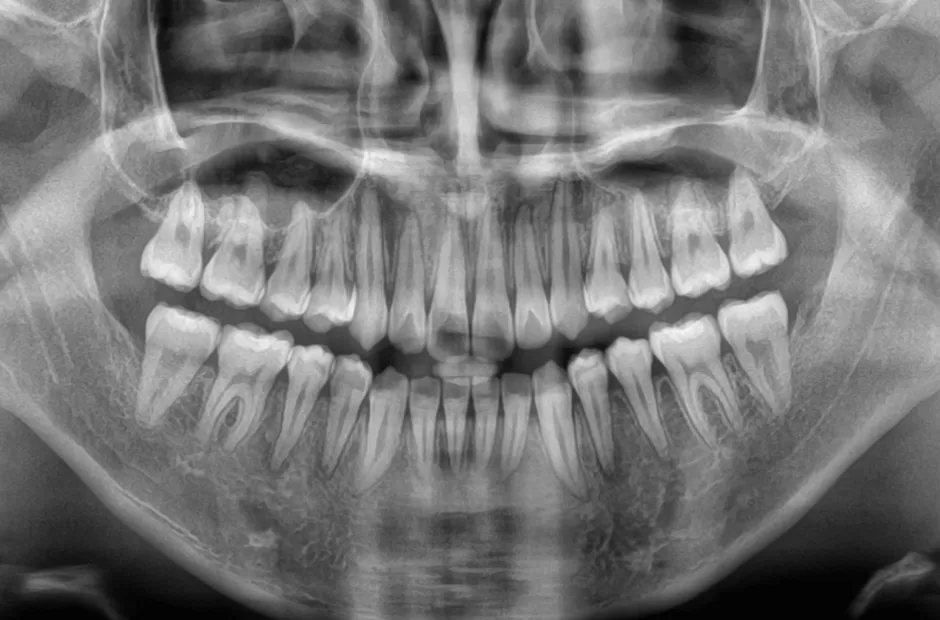

| 診断名・主訴 | 下顎前突、叢生 |

|---|---|

| 年齢・性別 | 23歳・女性 |

| 治療期間・回数 | 3年 |

| 治療に用いた主な装置 | 上顎5,5 下顎4,4 |

| 抜歯部位 | 舌側矯正 |

| 治療費 | 100万円(税抜) |

| リスク・副作用 | 装置による違和感・疼痛・歯肉退縮・歯根吸収・虫歯のリスクなど |